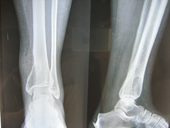

| Fracture Tibia pre op |

Fracture Tibia post op |

The Trauma Care Surgeons care for patients with recent or acute injuries as well as those who have chronic problems or complications of previous injuries such as delayed union and non union of fractures. Treatments are highly individualized and often include operative procedures as well as non-operative care such as splinting, bracing, and casting. Modern methods of surgery such as AO Fixation of Fractures , Interlocking Nailing of Fractures of Femur, Tibia and Humerus , LRS External fixation etc are routinely done . Rehabilitation after injury is a critical part of the treatment plan. Restoration of function, return to normal activities, and prevention of pain and deformity are our goals as we care for the total patient in a multidisciplinary environment.